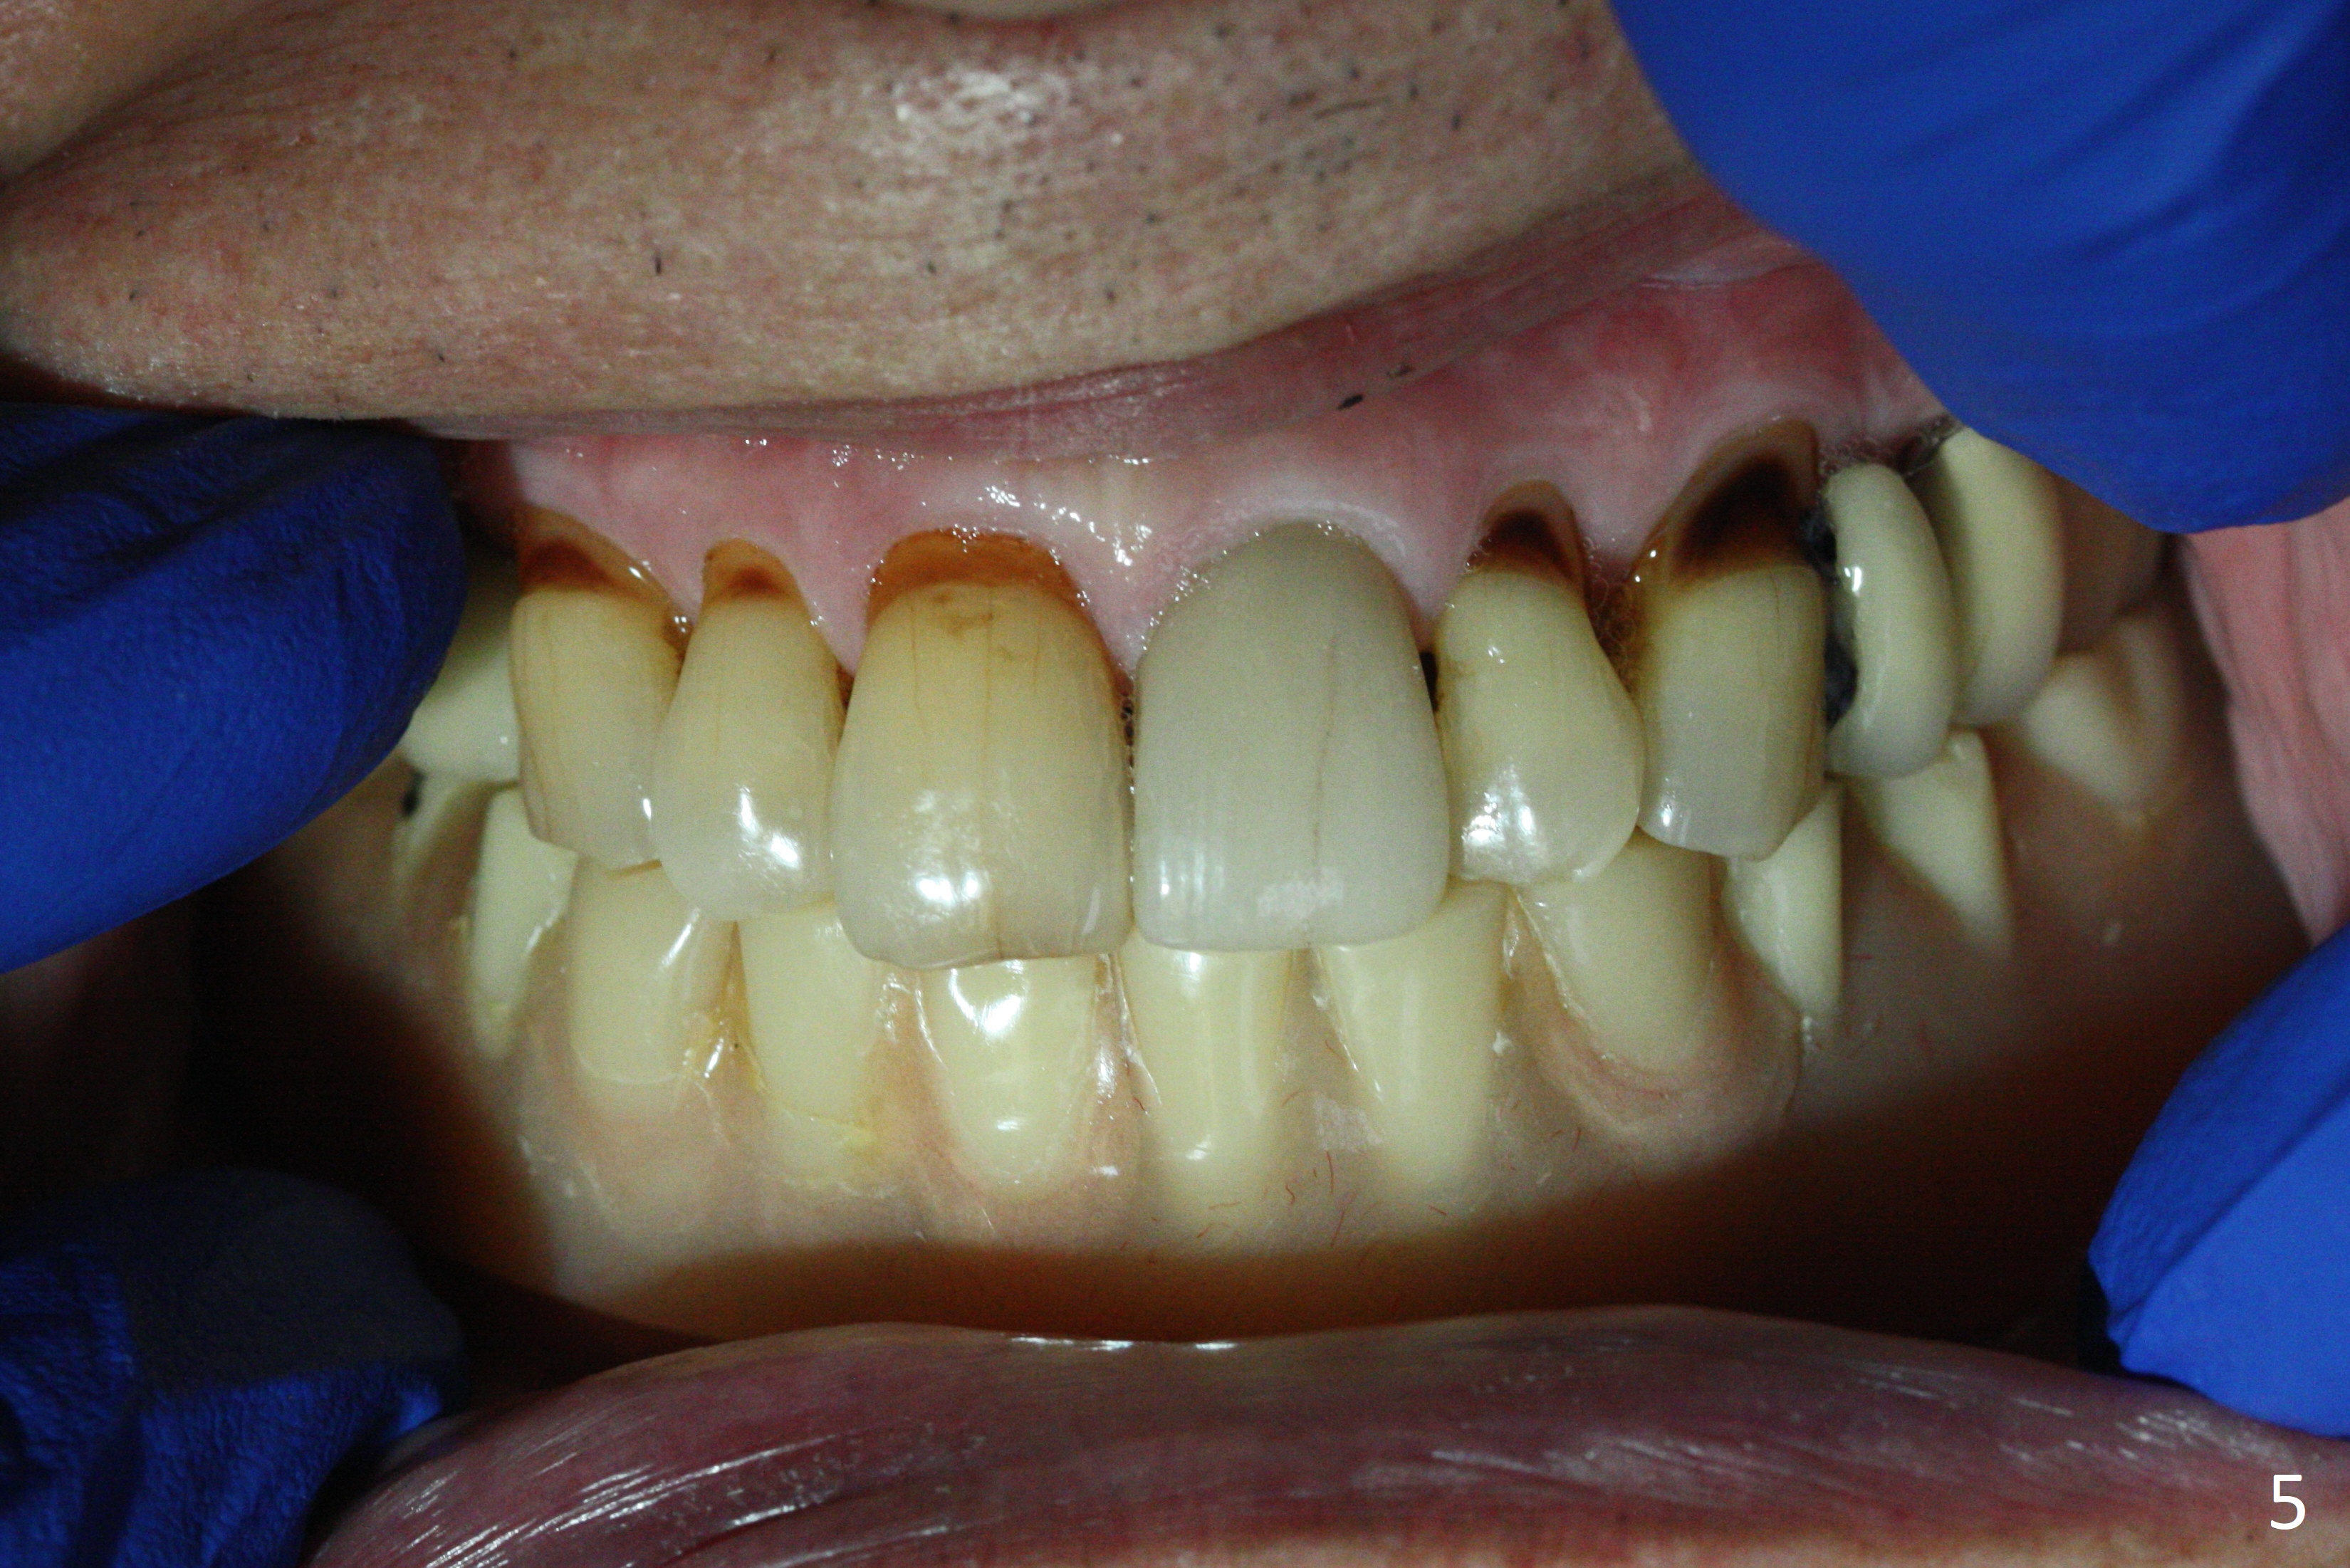

A 77-year-old man presents to clinic with chief complaint of loose lower denture, which is ~ 15 years old (Fig.1-6). The implants were placed ~ 30 years ago. There is wear and crack of the denture teeth (Fig.3). When the denture is remade, make metal occlusal surface at the premolar and molar region. An extra existing denture will be sent to lab for reference. What is the best method to take the lower impression? Block metal framework undercuts? Alginate or PVS?